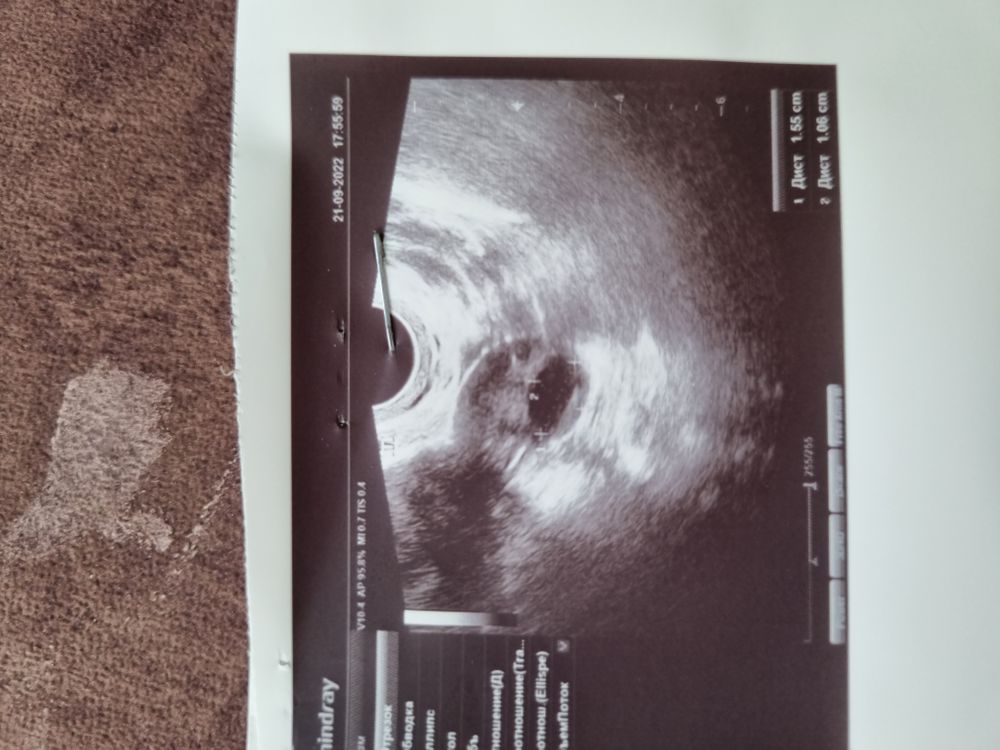

Update:

Похоже овуляция всё таки будет 😂👍

Вчера и сегодня.